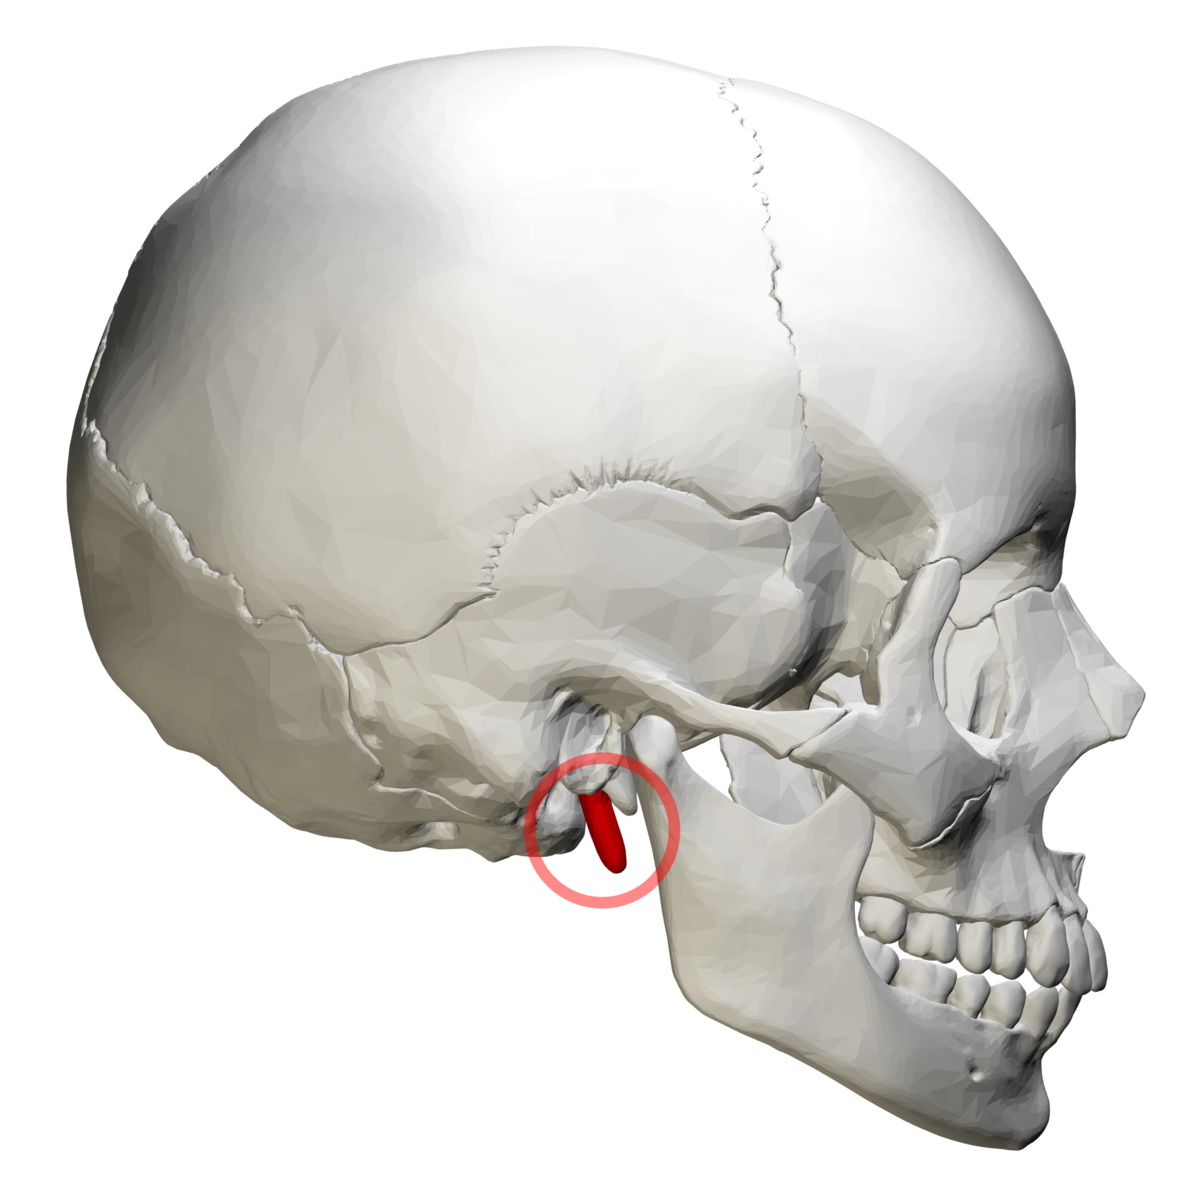

what is this, its description and its appearance on images- 9

hyoid bone

horseshoe shaped bone below mandible, between chin and thyroid cartilage

floating curved radiopacity, not seen intraoral